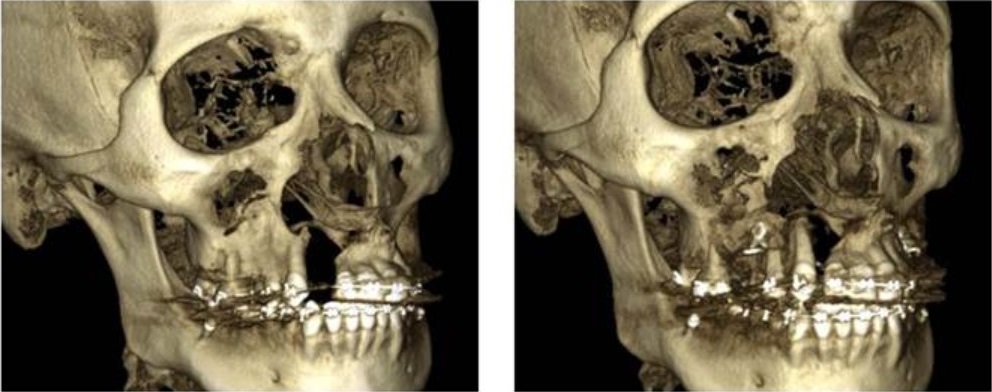

La reconstrucción 3D muestra buen contacto óseo y reducción completa de la fisura izquierda; en el lado derecho, falta tejido óseo radicular, pero el segmento se aproxima satisfactoriamente (Figura 4). En la comparativa de la reconstrucción 3D del lado derecho se observa la aproximación del segmento y la cercanía a nivel dental, sin embargo, debido a la anatomía que presentan los dientes adyacentes a la fisura y la cantidad de hueso alveolar en esta zona, es notable la falta de tejido óseo a nivel radicular para lograr mejor contacto (Figura 5). Del lado izquierdo se observa adecuado contacto a nivel óseo, dental y completa reducción de la fisura (Figura 6). Las fotografías clínicas confirman buena coloración, cobertura de tejidos blandos y reducción de la fístula palatina, logrando continuidad en el maxilar y cierre alveolar (Figura 7).